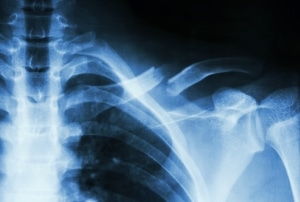

עצם הבריח

עצם הבריח (Clavicle או Collarbone) היא עצם ארוכה, דקה ומעוקלת (בצורת האות S), המחברת את הכתף אל עצם החזה. זוג עצמות הבריח נמצאות מעל הצלעות, וכל אחת מהן מחוברת לעצם השכמה (כתף) בצד אחד ולעצם החזה בצד השני. עם הבריח מהווה את החיבור הגרמי היחיד לכתף, מסייעת בהעברת כוח מהיד לחלק העליון של השלד ומגינה על כלי הדם והעצביים בדרכם לגפיים העליונות.

אבחון השבר נעשה על ידי בדיקה פיזיקלית וצילום רנטגן.